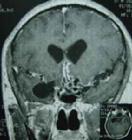

CTMRI檢查有助於鑑別診斷。